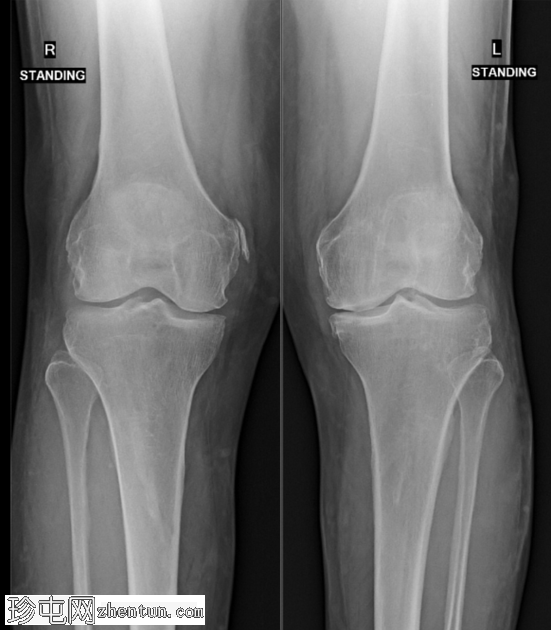

双侧膝关节内侧间室严重狭窄。关节面可见软骨下硬化和早期边缘骨赘形成。未见关节侵蚀。未见骨折或脱位。右侧股骨髁内侧可见一条弧形钙化,方向与内侧副韧带(MCL)的预期走行平行。

Pellegrini-Stieda损伤表现为股骨内侧的弧形钙化

它代表慢性MCL损伤,也可能是偶然发现的

通常X线平片足以诊断